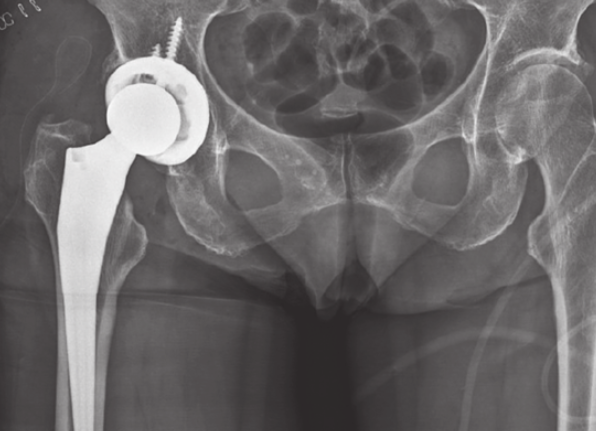

드물게 수술(예:인공관절) 후 합병증으로도 나타날 수 있습니다.

주로 증상과 이학적 검사로 진단하며, 필요시 MRI, 초음파, CT 등을 통해 다른 원인 감별 및 이상근의 상태, 좌골신경 압박 여부를 확인합니다.